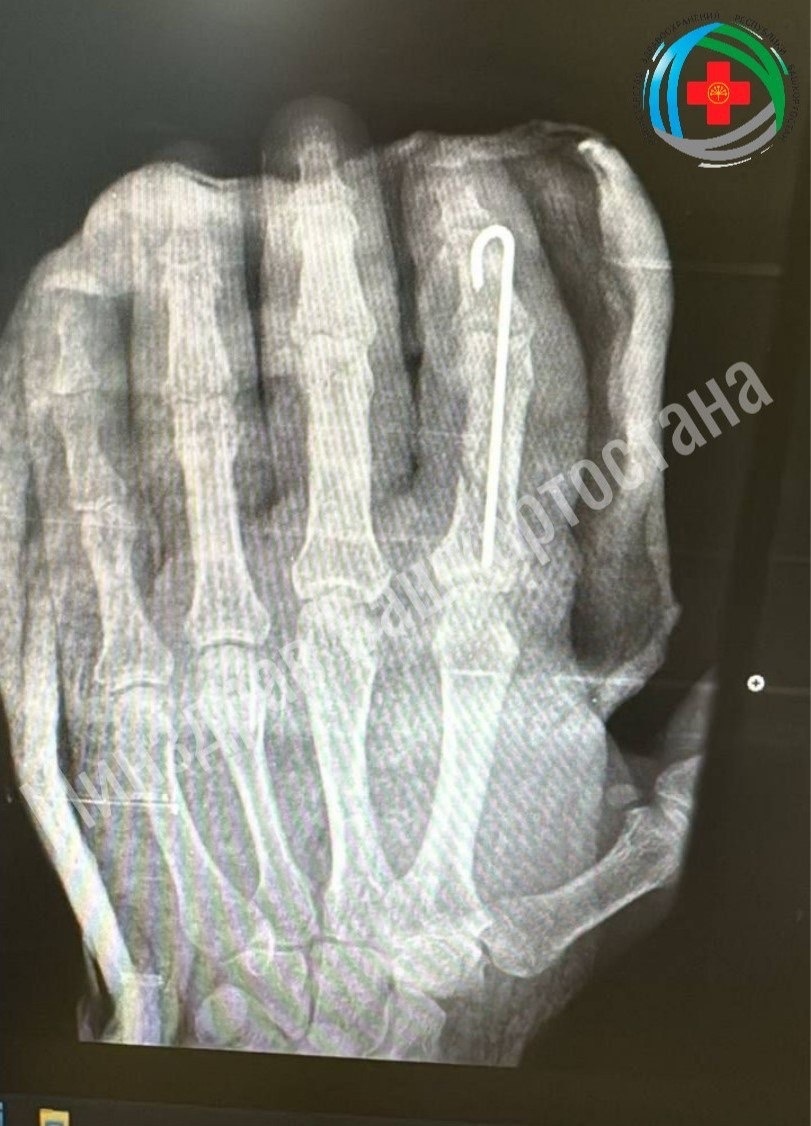

В больнице Башкирии успешно пришили отрубленный палец

Житель Благовещенска случайно отрубил себе палец топором во время работы во дворе. Врачи экстренно прооперировали его, проведя сложнейшую операцию: они восстановили крошечные сосуды, кость и ткани. В минздраве региона сообщили, что операция прошла успешно, палец прижился. Пациент уже начал двигать им и проходит курс реабилитации, который включает физиотерапию и ЛФК. Ожидается, что после восстановления функции пальца вернутся полностью.